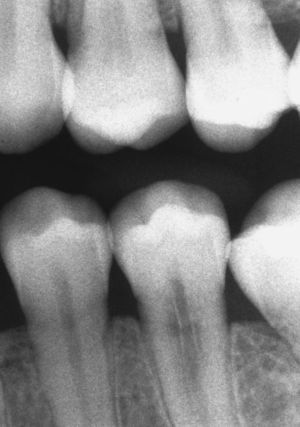

Características radiográficasDesde el punto de vista radiográfico, las reabsorciones externas (fig. 6) se caracterizan por los siguientes signos:

Luz del conducto radicular no dilatada.

Imagen radiolúcida en la zona radicular de límites irregulares.

Localización asimétrica.

La localización cambia con la proyección radiológica excéntrica.

Desaparición localizada del espacio periodontal.